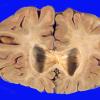

Subcortical Arteriosclerotic Encephalopathy (5)